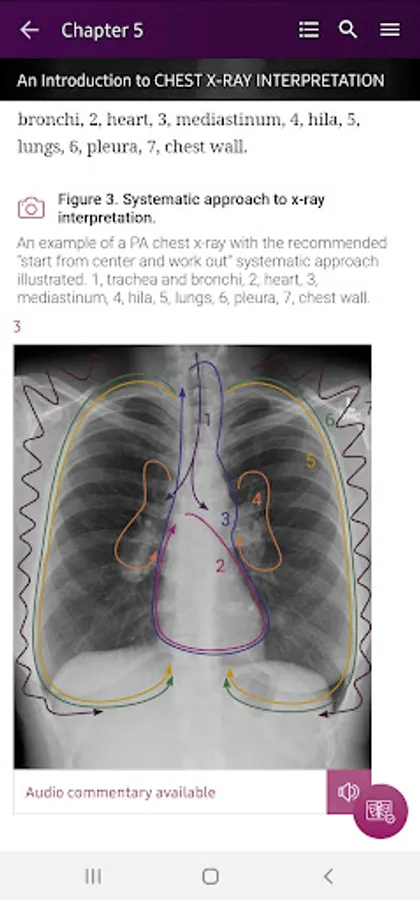

Section III* starts with a chapter on how to interpret the chest x-ray; this is where you begin to put your new knowledge into practice. Now that you know what to look for, you can do so in a systematic way to ensure the accurate identification of pathology.